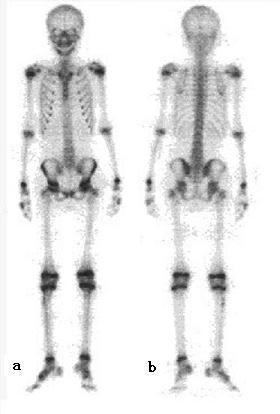

全身ECT骨显像 a.前位图;b.后位图